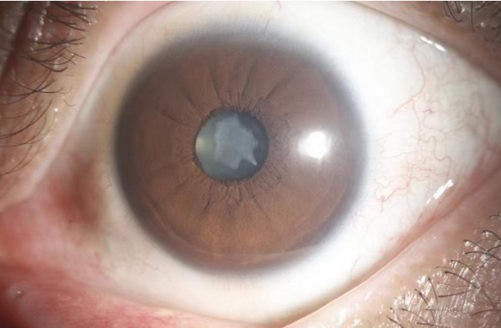

李先生的左眼前段照相

注:左图为李先生左眼的晶体前段照相

右图为正常的晶体前段照相

经检查,屈光手术中心肖迟主任告诉李先生,右眼视力0.15矫正0.8,左眼因晶状体浑浊明显,视力0.15只能矫正到0.3。不同于随着年龄增长而得的老年性白内障,这属于筋膜枪按摩眼球造成的外伤性白内障。